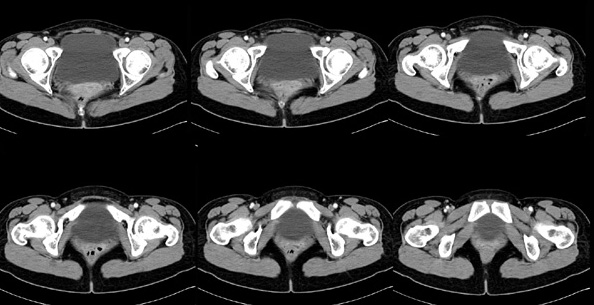

女性,28岁,停经3月,腹部膨隆1月,产前检查发现腹部占位

{肿块中心ct值27hu,增强后,动脉期、门脉期均无明显强化)

患者手术病理:腹腔囊性淋巴管瘤,象这样充满整个腹腔的的确很少见